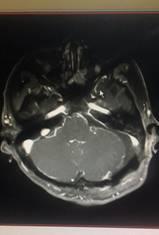

术前 术后

神经外科完成的两例听神经瘤手术中肿瘤位置在颅脑深部的桥小脑角区,该区域与负责我们人体的听力、面部感觉、闭眼活动、发声、吞咽、耸肩等活动相关的颅神经关系十分紧密,与面神经粘连在一起,特别是还与号称“外科手术禁区”和“生命中枢”所在的脑干紧密粘连,手术既要尽量全切肿瘤又要保护以上重要神经和结构,加之患者高龄,肿瘤体积大,手术风险和难度较普通听神经瘤手术高的多。